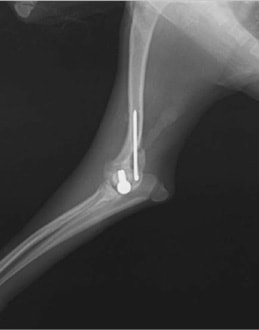

症例3:キルシュナーワイヤーのピンニングによる整復

ペルシャ猫 11ヶ月齢 雄

他院にて左大腿骨遠位の成長板骨折(salter-harrisⅠ型)が認められており、治療相談を目的として来院。当院にて、キルシュナーワイヤーを用いたピンニングにより骨折部位の整復を行いました。術後の経過は良好で、現在も経過観察中です。

術前レントゲン

術後レントゲン